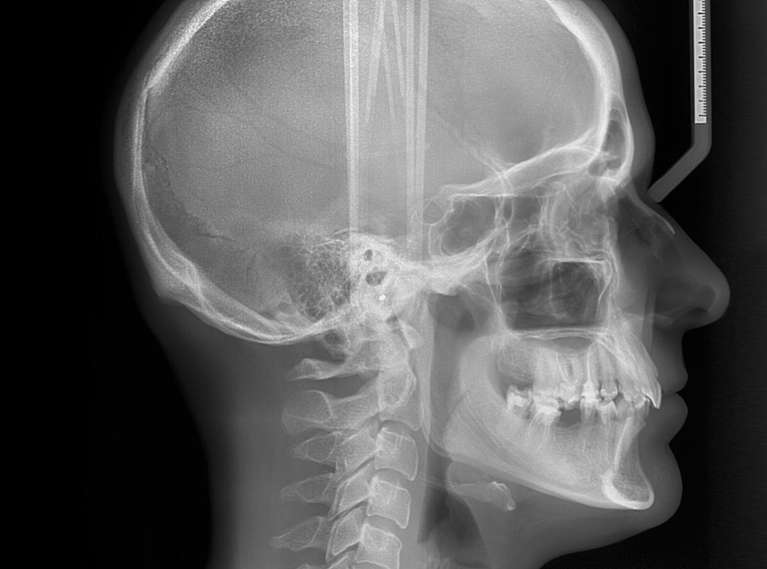

Cephalometric (Ceph) X-Ray

Cephalometric (ceph) x-rays are essential in orthodontics because they provide a side-image of the head to show teeth, jaw relation, and bone structure. This type of x-ray helps in planning treatment by evaluating the teeth's relation to the jaws and the jaws' relation to the head. With ceph x-rays, you benefit from a tailor-made approach to orthodontic care for more effective and lasting outcomes.